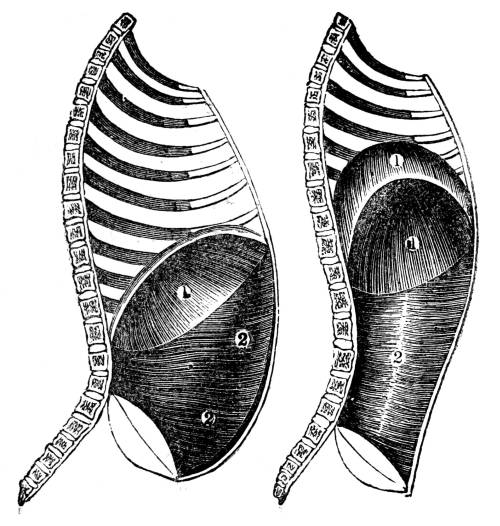

Fig. CXXXV.—

View of the Air Tubes and Lung.

1. The larynx. 2. Trachea. 3. Right bronchus. 4.

Left bronchus. 5. Left lung; the fissures denoted by the

two lines which meet at 6, dividing it into three lobes,

and the smaller lines on its surface marking the division of

the lobes into lobules. 7. Large bronchial tubes. 8. Minute

bronchial tubes terminating in the air cells or vesicles.